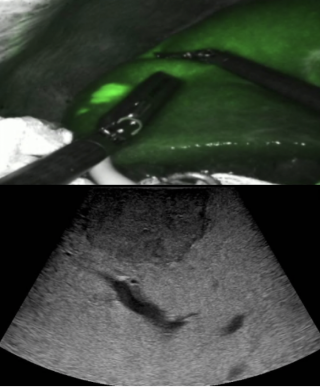

A 55-year-old overweight man presented with one week of right-sided abdominal pain with recent worsening despite outpatient medical therapy. He was hemodynamically stable but had right upper quadrant tenderness and localized guarding. Laboratory testing showed elevated C-reactive protein with a normal leukocyte count and normal liver biochemistry. CT demonstrated inflammatory fat stranding of the right greater omentum with a hyperdense rim, consistent with right-sided omental infarction (Figure 1). Because pain persisted despite conservative management, diagnostic laparoscopy was performed and confirmed ischemic omentum with hemorrhagic peritoneal fluid (Figure 2), and a normal gallbladder and appendix. Laparoscopic omentectomy was completed without complications. Histopathology confirmed omental infarction (Figure 3). The patient was discharged on postoperative day 1 and remained asymptomatic at 6-week follow-up.